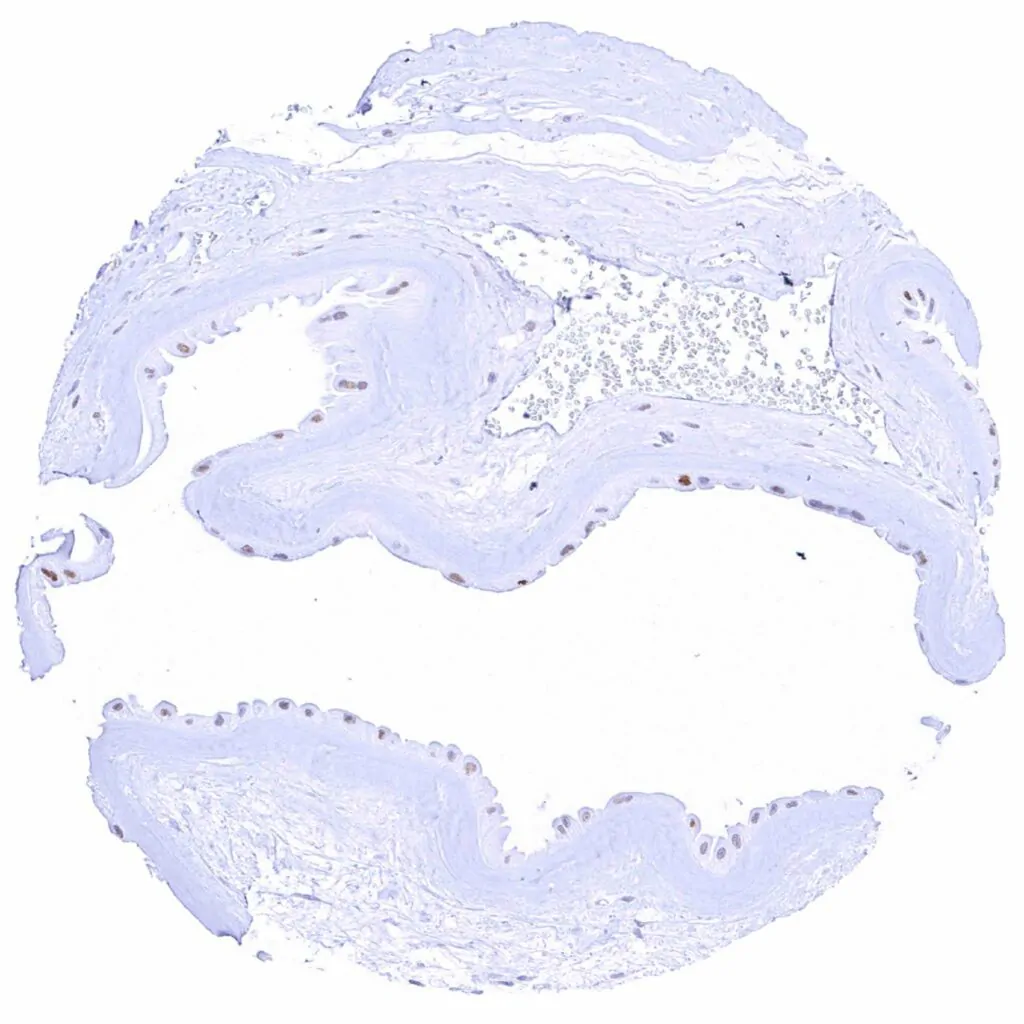

Kidney, pelvis, urothelium – Weak to strong Cyclin E1 staining of urothelial cells is limited to the top cell layers of the urothelium. The staining intensity increases towards the surface